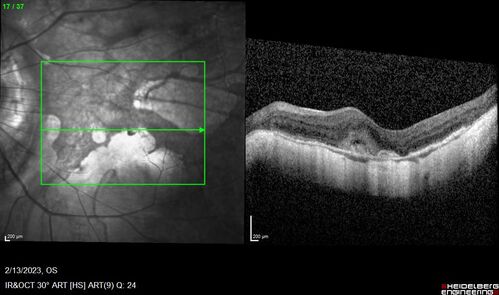

Myopic CNVM Left Eye

80 year old female. VA dropped to 20/125 but improved back up to 20/50 with Vabysmo

Myopic CNVM - Colobomas